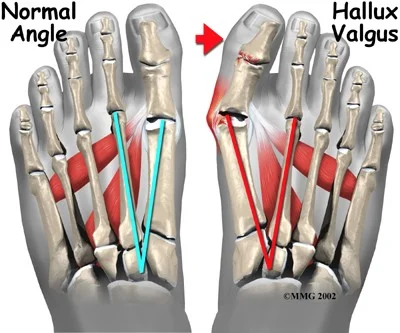

Hallux Valgus

- Definition: lateral deviation of the great toe (hallux) and medial deviation of the first metatarsal

Radiology - Hallux Valgus

- XR views:

- AP standing:

- Lateral deviation of big toe

- Increased varus of 1st MT

- Subluxation of MT-Phal. joint

Treatment - Hallux Valgus

Aim:

- Re-align the 1st metatarsal

- Correct valgus deformity of big toe

- Soft tissue balancing